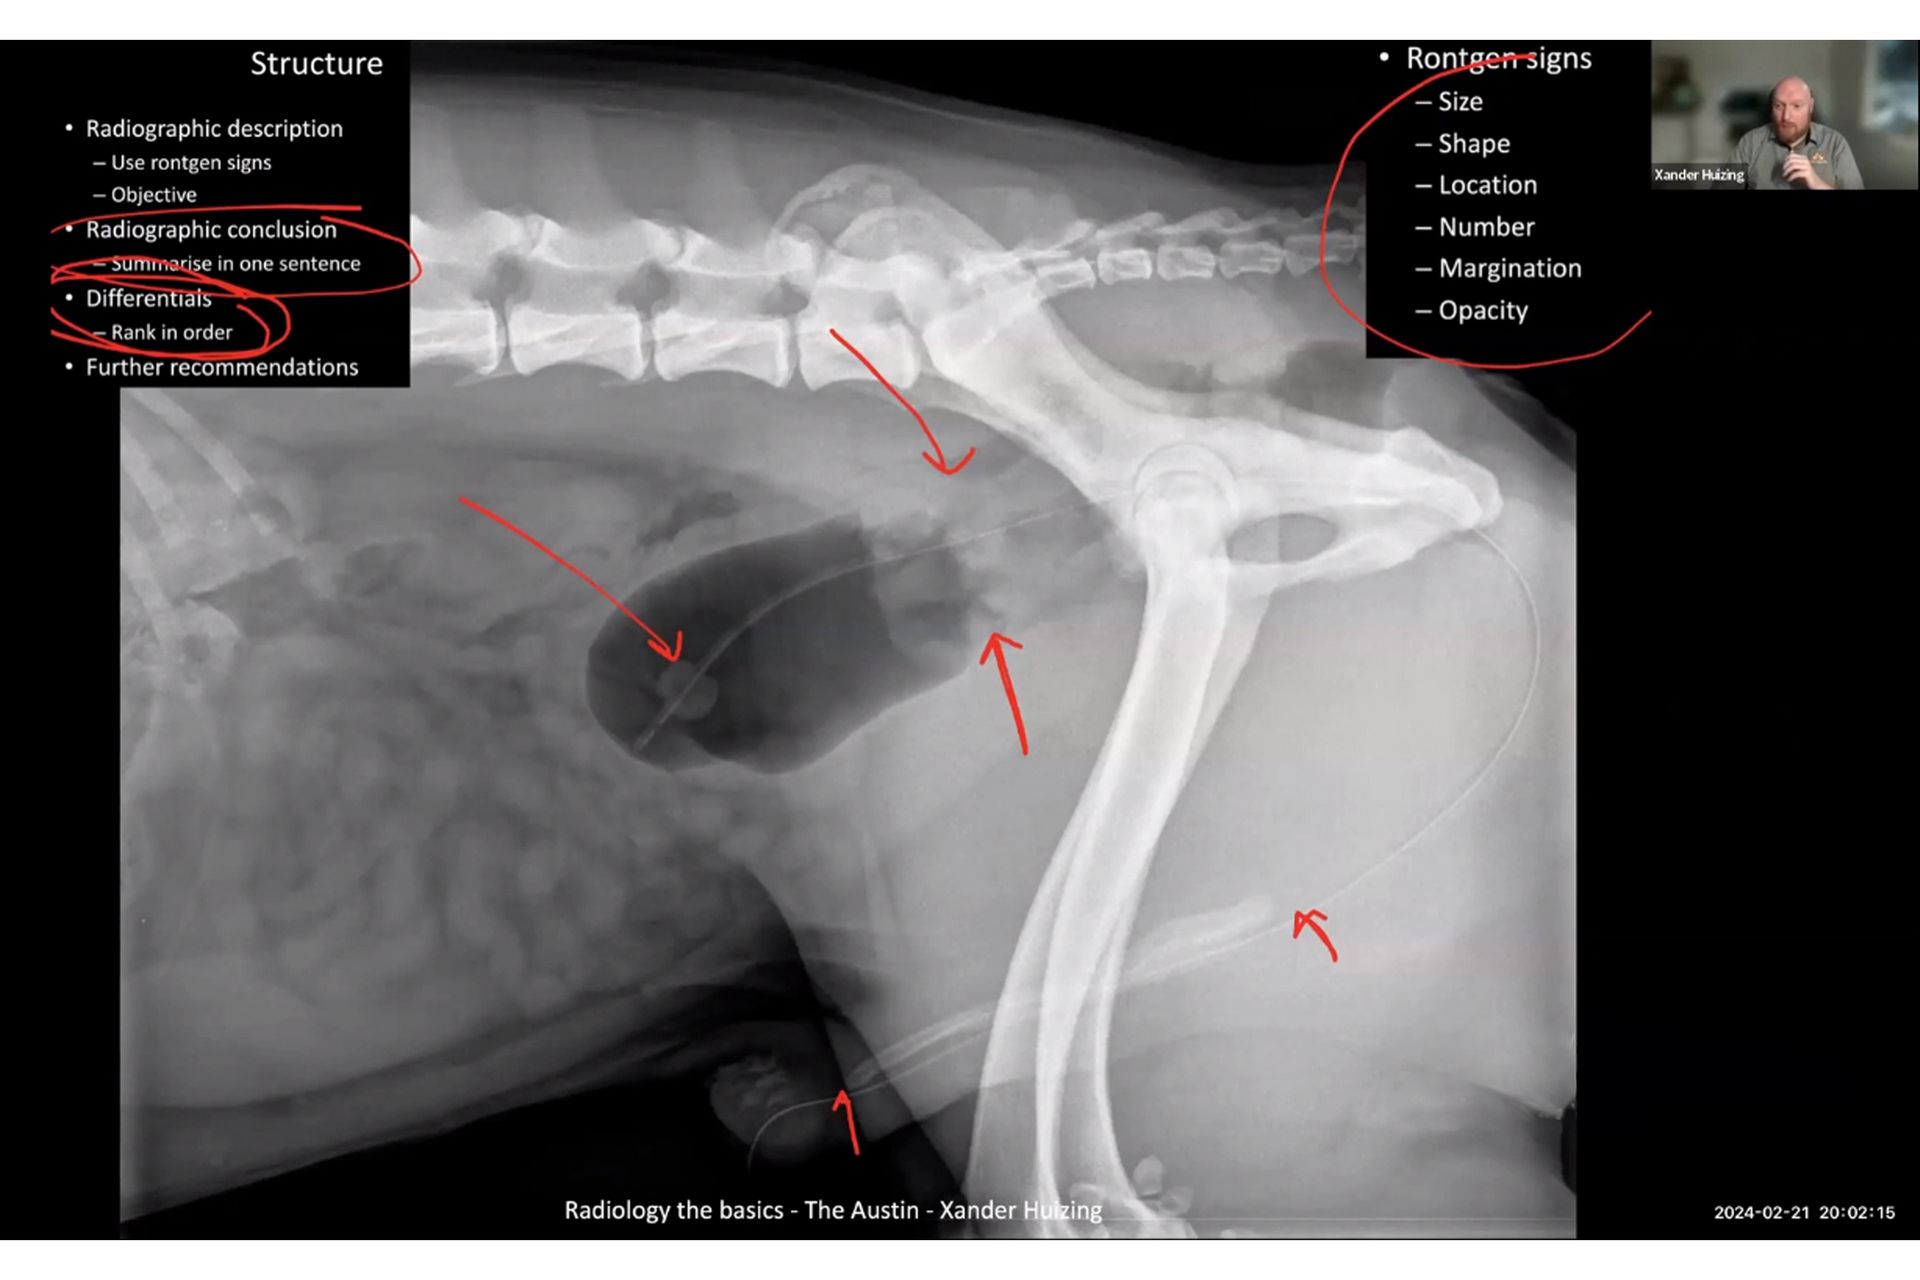

У заході прийняли участь науковці та  практикуючі лікарі ветеринарної медицини з усього світу. Спікером вебінару виступив Ксандер Хейзінг (DVM DipECVDI MRCVS), відомий сертифікований лікар із ветеринарної діагностичної візуалізації (DipECVDI) та клінічний радіолог, практикуючий спеціаліст з УЗД, рентгенографії, КТ, МРТ і флюороскопії. Доктор Хейзінг працював у реферальних та наукових колах в Австралії та Європі. Він є директором Остінської школи радіології тварин і надає послуги візуалізації ветеринарам Аделаїди та Південної Австралії.

Пан Ксандер провів майстер – клас з радіології та розповів про основні переваги даного методу дослідження, зокрема те, що сама процедура його проведення проста і не вимагає втручання в організм тварини і, в більшості випадків, не вимагає спеціальної підготовки і може бути виконана безпосередньо на прийомі у ветеринара для встановлення діагнозу, прогнозування перебігу захворювання, визначення його локалізації, спостереження динаміки результатів лікування.